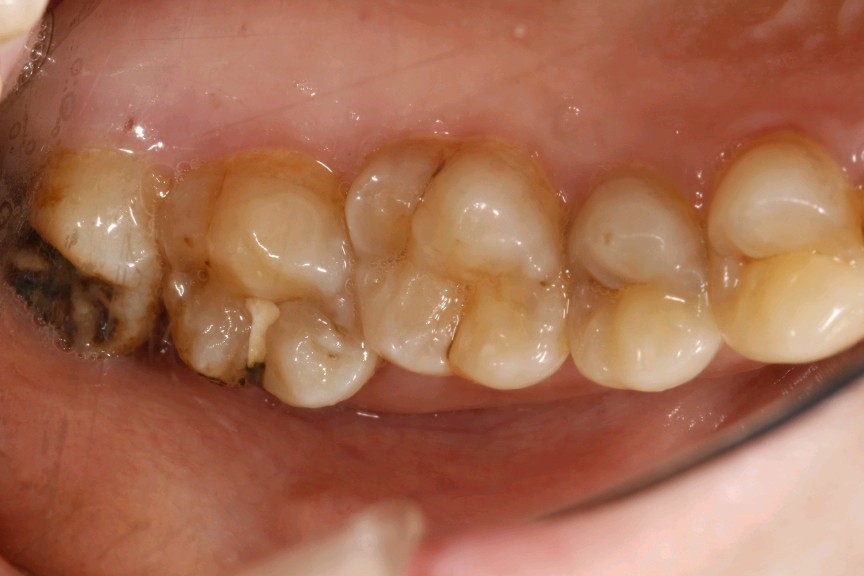

患者女,三十岁,右上后牙偶感食物嵌塞,前来我院就诊。检查发现患者前磨牙和后牙邻面发生了龋坏,询问得知患者平时没有使用牙线的习惯,进食后没有做好清洁,食物长久嵌塞在牙缝中,发生龋坏。邻面邻接关系一旦发生了一定的破坏,进食食物食物的时候就会出现食物嵌塞,食物嵌塞会刺激牙龈乳头,从而引起炎症出现疼痛。而邻面龋主要是因为牙缝难以清洁,长期菌斑食物残留,牙齿邻接面被细菌侵蚀,慢慢缺损,因为位置比较隐蔽,不易发现,当发现的时候,缺损往往比较大了。为了更好的恢复邻接关系,所以建议这位患者嵌体修复。

术前